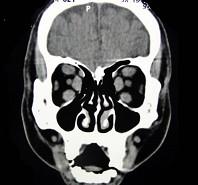

问题 女性50岁,消瘦、多饮多食,脖子粗大,双侧眼球突出,一年余,CT检查如图所示,应考虑为 ( )

选项 A、横纹肌肉瘤 B、眶部结核 C、甲状腺眼病 D、炎性假瘤 E、眼型格氏病

答案 C